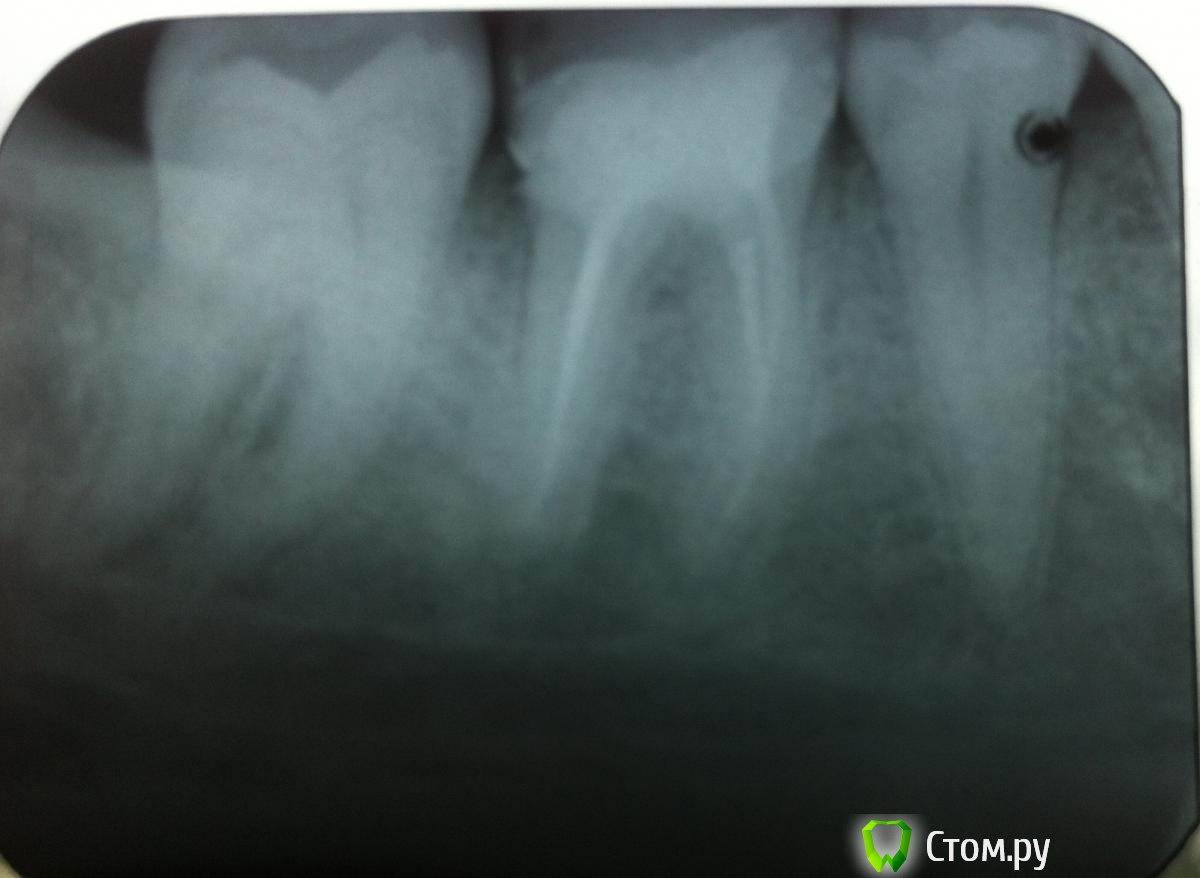

Aalsol Опубликовано 3 июня, 2014 Автор Поделиться Опубликовано 3 июня, 2014 может эти получше. У меня к сожалению есть негатив только. цифрового снимка нет((( Ссылка на комментарий

red_butler Опубликовано 4 июня, 2014 Поделиться Опубликовано 4 июня, 2014 Если судить, только по снимку - зуб можно вылечить, сходите на консультацию к стоматологу-эндодонтисту Ссылка на комментарий

DokDent Опубликовано 4 июня, 2014 Поделиться Опубликовано 4 июня, 2014 Как раз он и говорит что надо удалять. Мы начали делать коронку на него. Сейчас стоит временная. Ну и вот в это воскресенье зуб заболел. Как я писал выше на десне появилось уплотнеие! Но боль вся прошла! Ну раз он заболел - он сказал надо удалять - толку не будет ((((( типа или через трещинку попадает микробы. Или на корне как он говорит воспалилась гранулема. К сож я снимки не понимаю и ни чего не могу сказать есть гранулема или нет!Проблема не в гранулёме. Проблема в трещине. Как она проходит и где заканчивается по Вашему снимку не видно (На рвг определяется далеко не всегда). Возможен перелом и с коронкой. Исчезновение боли не показатель благополучного исхода. Ссылка на комментарий